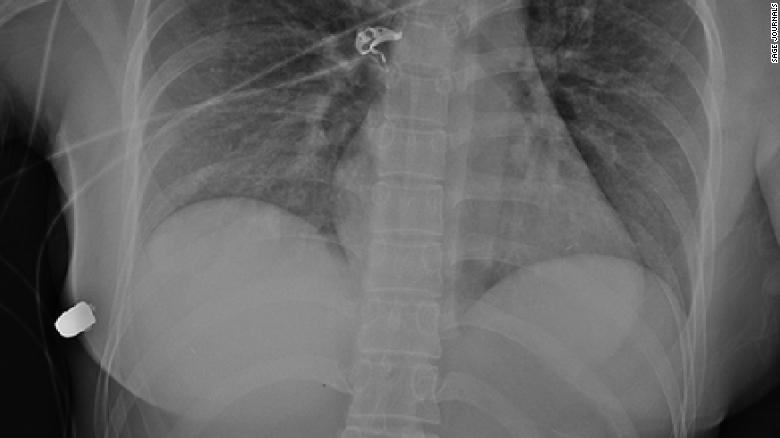

ภาพเอ็กเรย์แสดงกระสุนที่ทะลุไปที่เต้านมด้านขวา

แพทย์พบวัตถุที่มีลักษณะคล้ายกระสุนในผนังทรวงอกด้านหน้าล่างขวาของผู้หญิงด้านล่างเต้านมด้านขวา การเอ็กเรย์จากการบาดเจ็บแพทย์สามารถตรวจพบกระสุนที่ผนังด้านข้างทรวงอกด้านขวาซี่โครงหักและฟองอากาศที่เต้านมด้านซ้ายและสรุปว่ากระสุนเดินทางจากเต้านมซ้ายไปยังผนังทรวงอกขวา แพทย์กล่าวในภายหลังว่าผู้ป่วยได้รับการประเมินและเคลียร์โดยแพทย์ผู้บาดเจ็บ แต่ปืนไม่เคยหายและปืนยังไม่ทราบตามรายงาน พวกเขาตั้งข้อสังเกตในรายงานว่า แพทย์ทำการรักษาแผลโดยการถอดรากฟันเทียมการล้างแผลและใช้ยาปฏิชีวนะโดยใช้เวลาไม่นานมาก